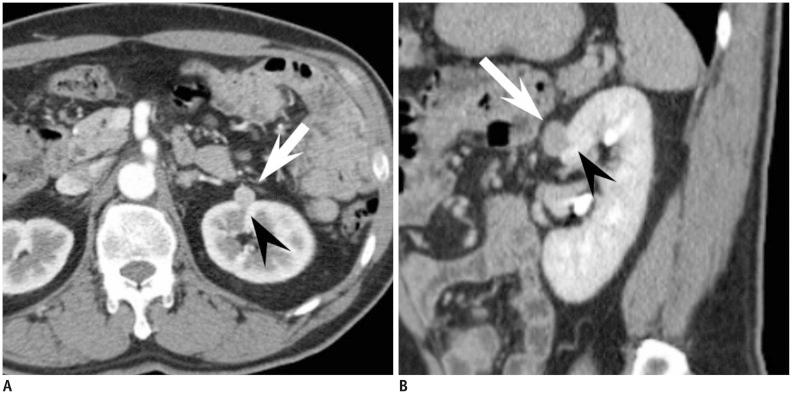

The prevalence of small renal masses (SRM) has risen, paralleling the increased usage of cross-sectional imaging. A large proportion of these SRMs are not malignant, and do not require invasive treatment such as nephrectomy. Therefore, differentiation between early renal cell carcinoma (RCC) and benign SRM is critical to achieve proper management. This article reviews the radiological features of benign SRMs, with focus on two of the most common benign entities, angiomyolipoma and oncocytoma, in terms of their common imaging findings and differential features from RCC. Furthermore, the role of percutaneous biopsy is discussed as imaging is yet imperfect, therefore necessitating biopsy in certain circumstances to confirm the benignity of SRMs.